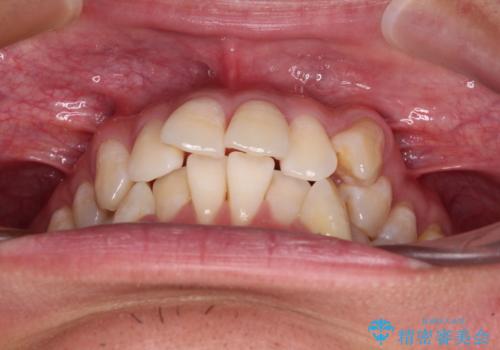

- 八重歯と飛び出している前歯を気にして来院された患者様です。

歯列としてはインビザラインでもワイヤー矯正でも対応できるものでしたが、上顎の八重歯や下顎小臼歯の捻転といったインビザラインでは時間のかかってしまう歯列不正が認められたため、補助装置やワイヤー矯正を治療当初に使用することで、インビザラインによる治療をスムーズに行えるように計画しました。